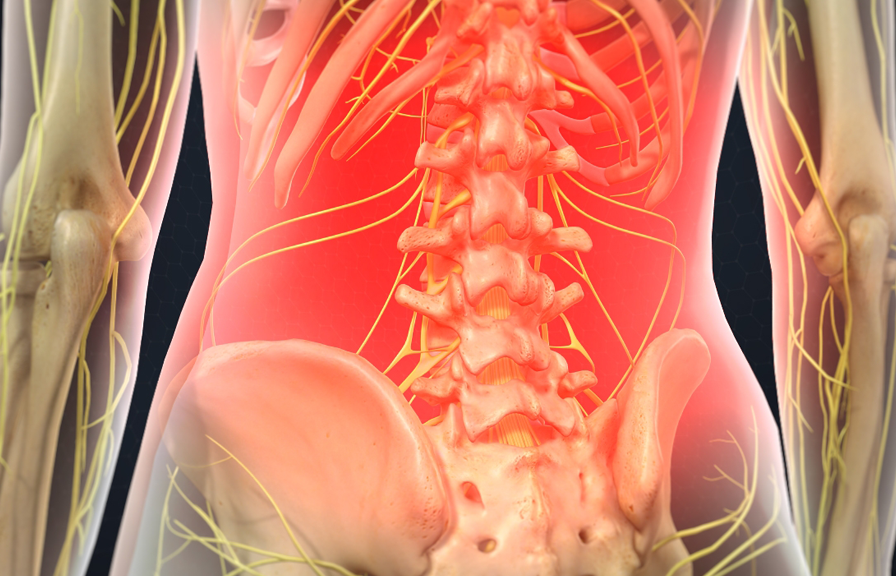

Have you had a back or neck surgery? Do you still have pain? If you suffer from chronic pain due to:

- Failed back surgery

- Spinal Stenosis

- Pinched Nerves

- Sciatica

At St. George Spine and Pain Institute the patient is our main priority. Chronic pain forces millions of people to live in misery by slowly dictating what they can and cannot do, whether it’s just preventing them from a daily walk, to enjoying activities with friends and family. Click here to read more.